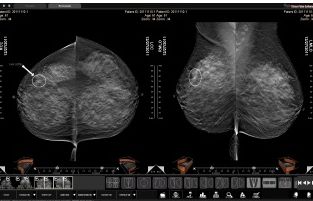

Oprogramowanie do skriningu i diagnostyki w mammografii

Oprogramowanie Three Palm Software zostało zaprojektowane we współpracy z czołowymi radiologami zajmującymi się mammografią (m.in. Doktorem Laszlo Tabarem) w taki sposób, aby zapewnić lekarzom rzeczywiste ułatwienia w ich codziennej pracy. Dwie podstawowe cechy wyróżniające Three Palm Software to szybkość oceny badania oraz nowatorskie narzędzia pomocne w wykryciu zmian w tkance.

Przechodzenie pomiędzy ważnymi w ocenie obszarami obrazu jest w programie bardzo płynne. Lekarz może swoją uwagę w pełni poświęcić diagnozie według zaplanowanych procedur oceny piersi. Prowadzony jest on przez program „za rękę” już od momentu wczytania badania, poprzez ocenę ważnych obszarów obrazu, aż po utworzenie raportu.

Po konsultacjach z czołowymi europejskimi radiologami od mammografii, twórcy programu wprowadzili pomocne narzędzia do oceny obrazów. Znajdują się wśród nich, między innymi, specjalne maski anatomicznych części piersi (skośnie, poziome oraz pionowe), oparte o technikę oceny Doktora Laszlo Tabara. Pomagają one uwidocznić diagnostycznie istotne, asymetryczne zmiany w tkance, w rejonach o największym prawdopodobieństwie ich wystąpienia.

Unikalna metoda lupy o zmiennym rozmiarze pozwala na wygodne obejrzenie wszystkich pikseli na zdjęciu, w pełnej rozdzielczości, w jak najszybszym tempie. Program automatycznie dzieli obraz piersi na sektory i śledzi już obejrzane piksele. Lekarz może dzięki temu w łatwy sposób obejrzeć całe zdjęcie w poszukiwaniu mikrozwapnień, bez zbędnego powtarzania lub omyłkowego omijania niektórych pikseli.

Oprogramowanie Three Palm Software pracuje także na obrazach z tomosyntezy, bezpośredniej i pośredniej radiografii, USG, MRI oraz CT. Obrazy pobierane są na stację w tle. Lekarz nie musi więc czekać na wczytanie kolejnego badania, ale od razu może przejść do jego oceny.